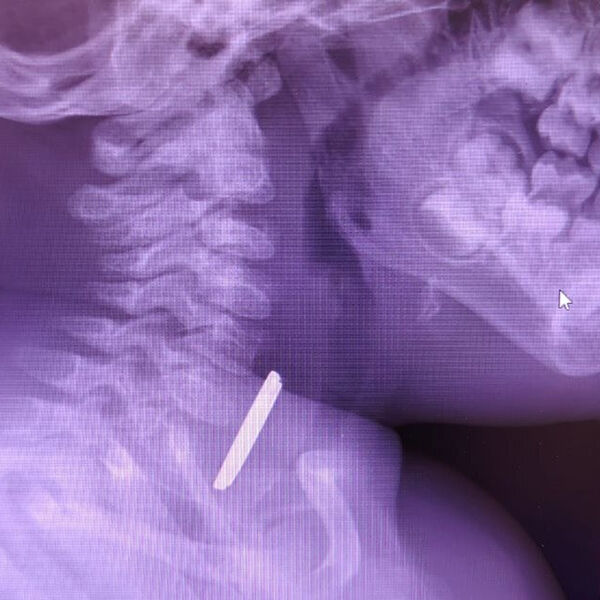

Врачи окружной детской больницы в Нижневартовске спасли годовалого ребенка, который проглотил батарейку. Об этом сообщили в пресс-службе медицинского учреждения.

Маленький пациент поступил в больницу с затрудненным глотанием и слюноотделением. Ребенка направили на рентген, который показал наличие батарейки в верхней трети пищевода. Пациента направили направили на экстренную операцию, и под наркозом извлекли предмет, который уже успел причинить здоровью младенца вред.

«Батарейка повредила стенку пищевода, вызвав глубокий электрохимический ожог, занимающий половину просвета пищевода. Учитывая тяжесть состояния от полученной травмы, ребенок был госпитализирован в отделение реанимации, где проводилась интенсивная терапия», — рассказал детский хирург детской больницы Вячеслав Воронин.